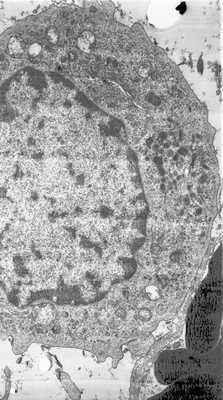

При гранулематозном иридоциклите в основном очаге наблюдаются лейкоциты в большом количестве, мононуклеарные фагоциты, эпителиальные, гигантские клетки и зону некроза.